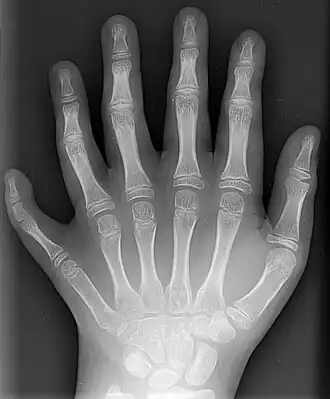

Hexadactylie

Hexadactylie of hexadactylisme (Oudgrieks: hex (ἕξ) = "zes" en daktulos (δάκτυλος) = "vinger") is de benaming voor het voorkomen van zes vingers aan een hand of van zes tenen aan een voet. Het is de meest voorkomende vorm van polydactylie.